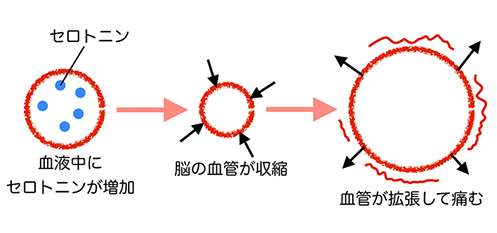

まずは片頭痛のメカニズムから考えていきましょう。片頭痛のしくみでお伝えしたように、脳血管内にセロトニンという物質が放出されて血管が収縮する事から始まります。その後セロトニンが減少した時に、血管が拡張してズキンズキンと痛みます。